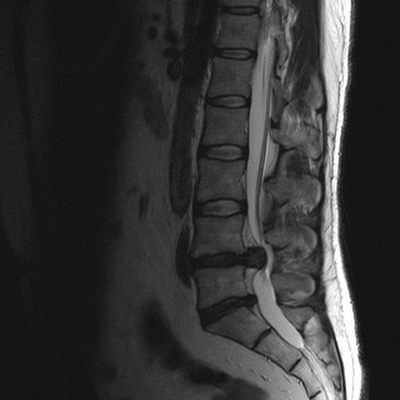

Снижение высоты диска, секвестрированная грыжа в области тел L4-L5 и абсолютный стеноз спинномозгового канала на МРТ снимке поясничного отдела позвоночника в сагиттальной проекции

МРТ позвоночника. Сагиттальная Т2-взвешенная МРТ, срединный срез поясничного отдела. Показана нумерация позвонков, измерения позвоночного канала (черная линия). Т- дуральный мешок с ярким ликвором. L- желтая связка. Sacrum - крестец. D - межпозвоночный диск. Голубым выделен остистый отросток, желтым - тело позвонка, Голубые точки - ход корешков.

МРТ позвоночника. Парасагиттальная (околосрединная) Т2-взвешенная МРТ поясничного отдела. Красными стрелками показаны корешки.